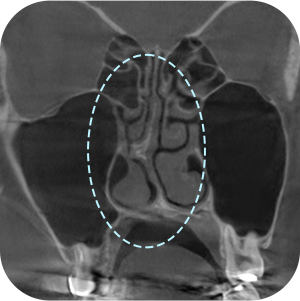

Apakah perlu dilakukan CT scan hidung?

AKarena ini adalah operasi revisi, kita perlu mendiagnosis dengan lebih tepat!

Analisis menyeluruh penting untuk operasi revisi hidung .

Karena analisis yang akurat

dapat dilakukan melalui 3D-CT! - 03